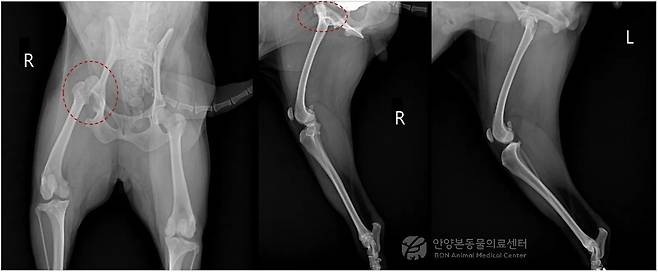

추가 방사선 검사 결과, 우측 대퇴골두가 정상적인 관골구 위치에서 이탈해 전방 등 쪽으로 완전히 변위된 상태였다. 외상에 의한 고관절 탈구가 의심됐다. 퇴행성 관절염이나 구조적 손상이 뚜렷하지 않아 의료진은 관절을 최대한 보존하는 방향의 수술적 치료를 결정했다.